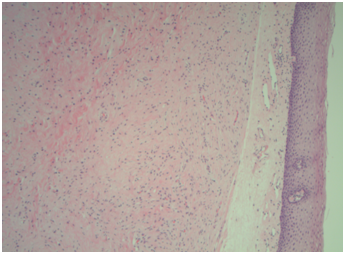

The pathological outcome for both tonsils was lymphoid hyperplasia. Gross examination for the left soft palate mass showed a pink-tan, soft, multilobulated, polypoid portion of smooth, shiny, rubbery tissue that measured 3.0 x 2.7 x 2.0cm. A sectioned portion of the specimen revealed multinodular, tan, rubbery, whorled cut surfaces (Figure 1 & 2). The initial pathologic diagnosis of the left soft palate mass was a benign plexiform lesion, however, the negative staining for S100 (Figure 3) and positive staining for smooth muscle actin (Figure 4) suggested myofibroblastic differentiation. Morphological features of the mass suggested a plexiform neurofibroma. Hence, combining the morphologic appearance with the findings from the Immunostains a new diagnosis favored plexiform leiomyoma.

Figure 2 Soft palate plexiform leiomyoma. (Hematoxylin and Eosin stain, Magnification x 400).